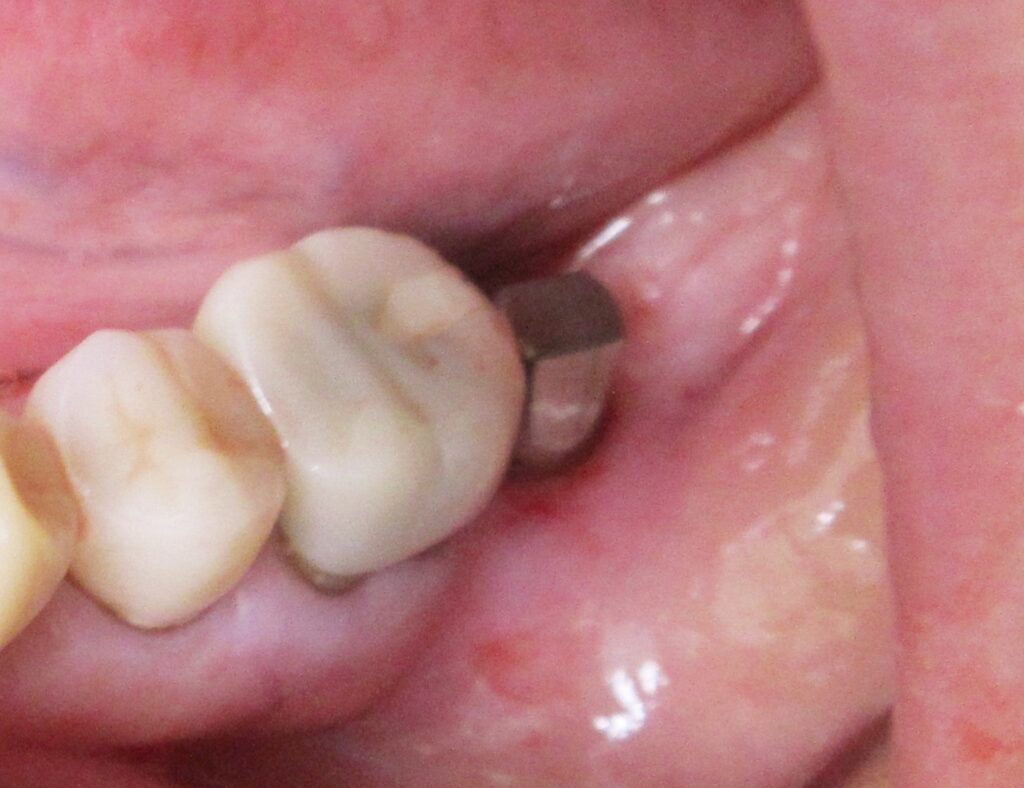

今回の患者様はインプラント植立を希望され、左下7番目、1本の植立が決まりました。

左下7番目の歯茎から骨の部分までを穴開けパンチの要領で穴を開けていきます。

開けた穴に、専用道具を使ってネジを締めるように長さ2センチ程のインプラントを骨に埋め込んでいきます。

しっかりとインプラント埋め込まれた後は、動揺がないか、噛んだ時に当たらないかなどを確認して、最後にパノラマ写真を撮影して今回のオペは終了となりました。